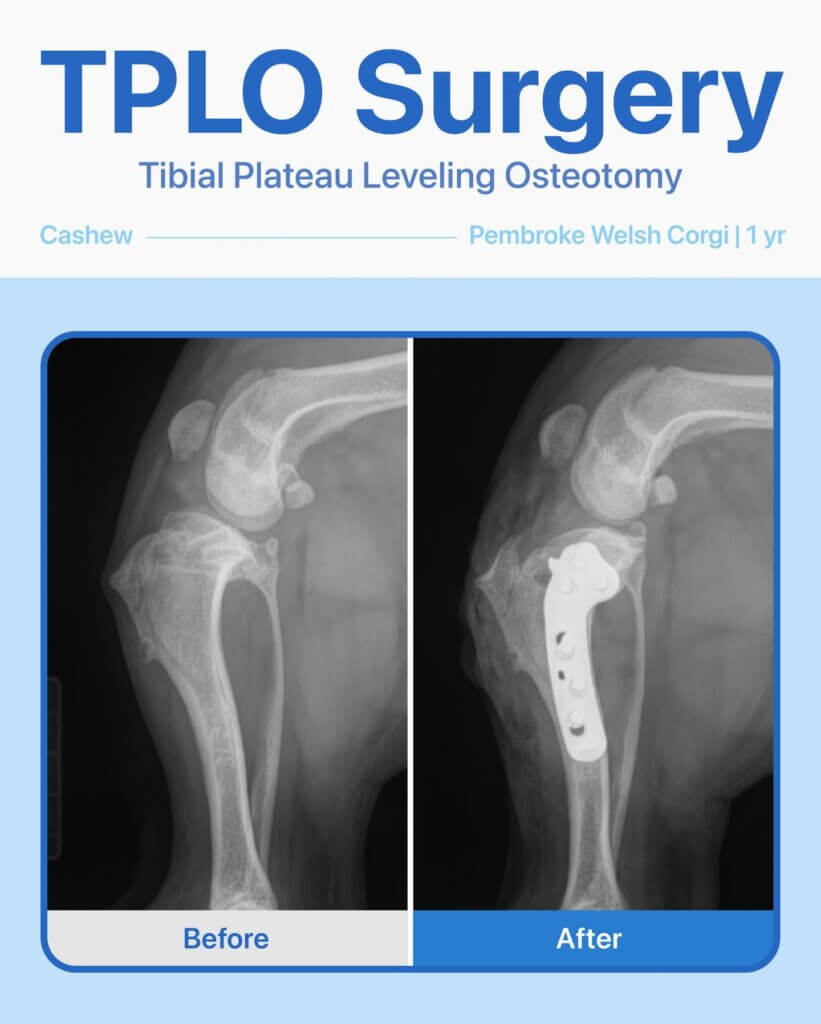

After radiographs and a thorough exam, we discovered he had a cruciate ligament tear and would need TPLO surgery to get him back on his feet. Before the procedure, we ran blood tests to make sure he was healthy—and everything looked great.

The surgery went smoothly, and Cashew has been healing beautifully! He’s a brave little pup, and it’s been amazing to watch him recover and get back to his playful self.